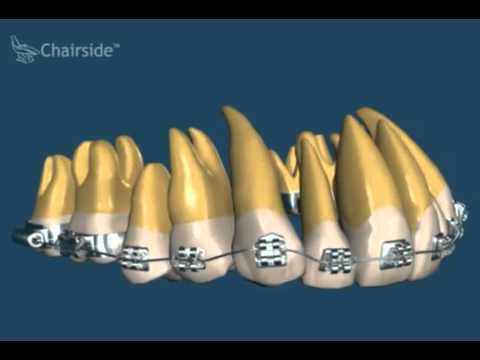

Что такое дуги на брекетах? Зачем они нужны? И зачем их менять?

Как работает брекет-система? Как брекеты выравнивают зубы. Зачем нужно менять дугу у брекетов?